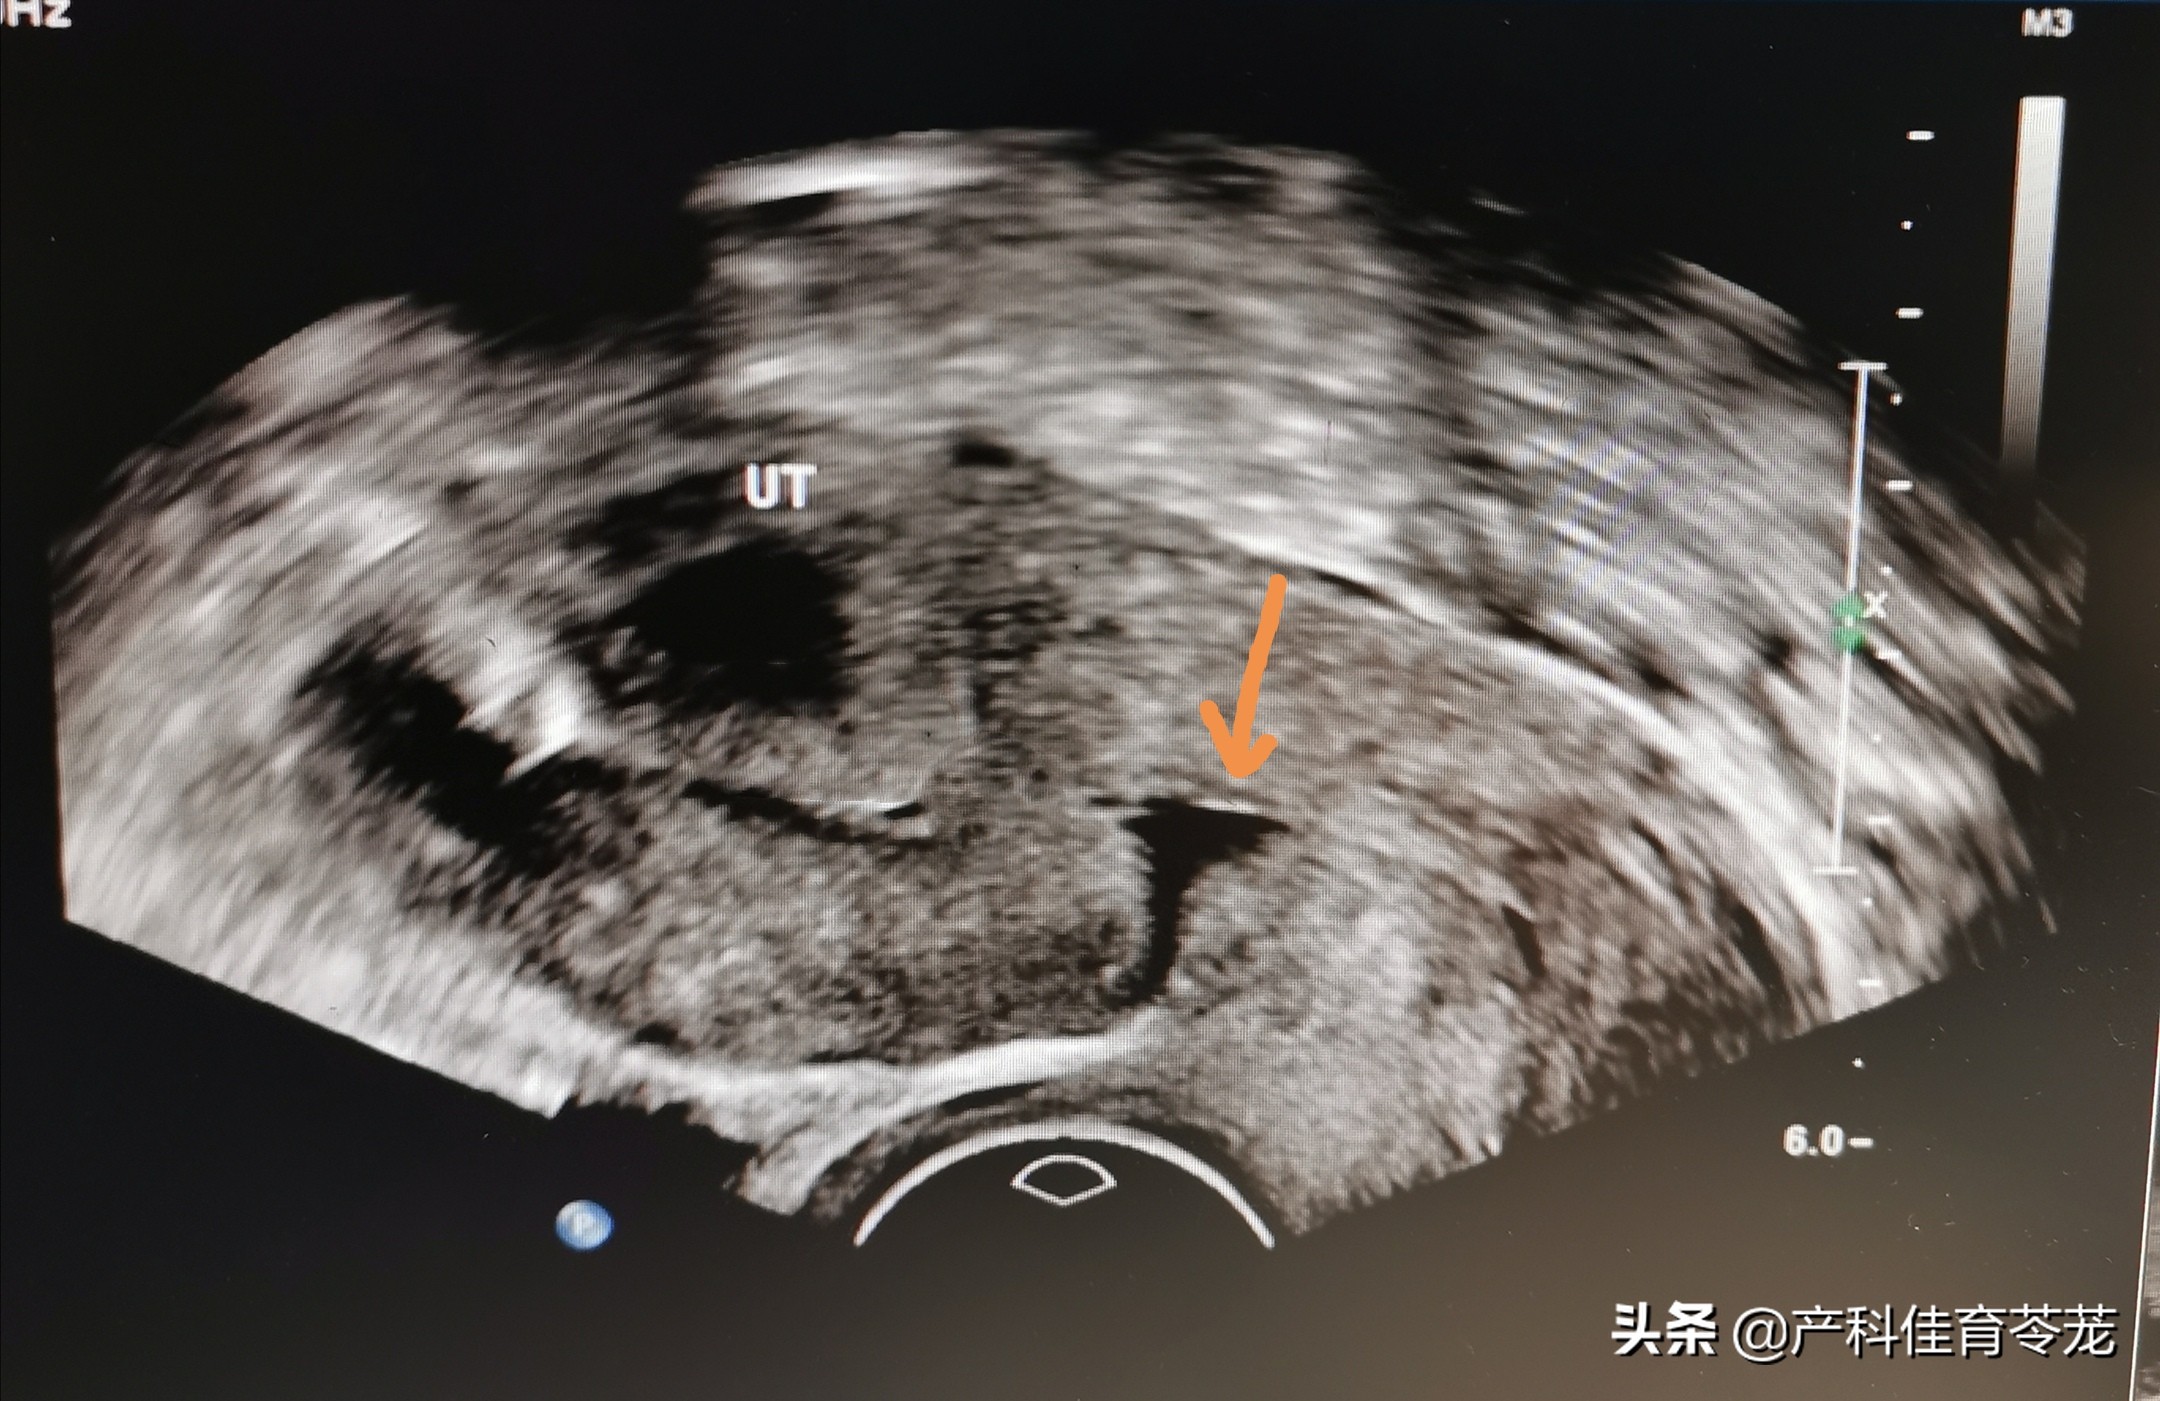

起初,李某以为是术后还没有完全恢复正常,没有在意,但是一年过去了依然如此,于是到医院做了检查,B超是这样的:

医生告诉她上图中箭头所指的地方是”瘢痕憩室“,这就是导致月经老是不干净的原因。